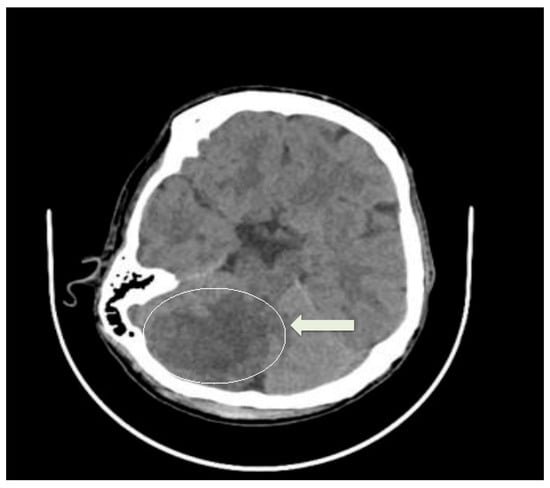

2. Case Presentation